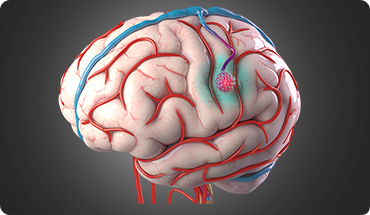

Aneurysms

A brain aneurysm is the ballooning of a weak area on the wall of an artery in the brain. An aneurysm can leak or rupture causing blood to escape into the brain. This is an emergency condition as the blood can damage brain tissue and increase pressure inside the skull, disrupting oxygen supply to the brain, which can lead to unconsciousness or even death.